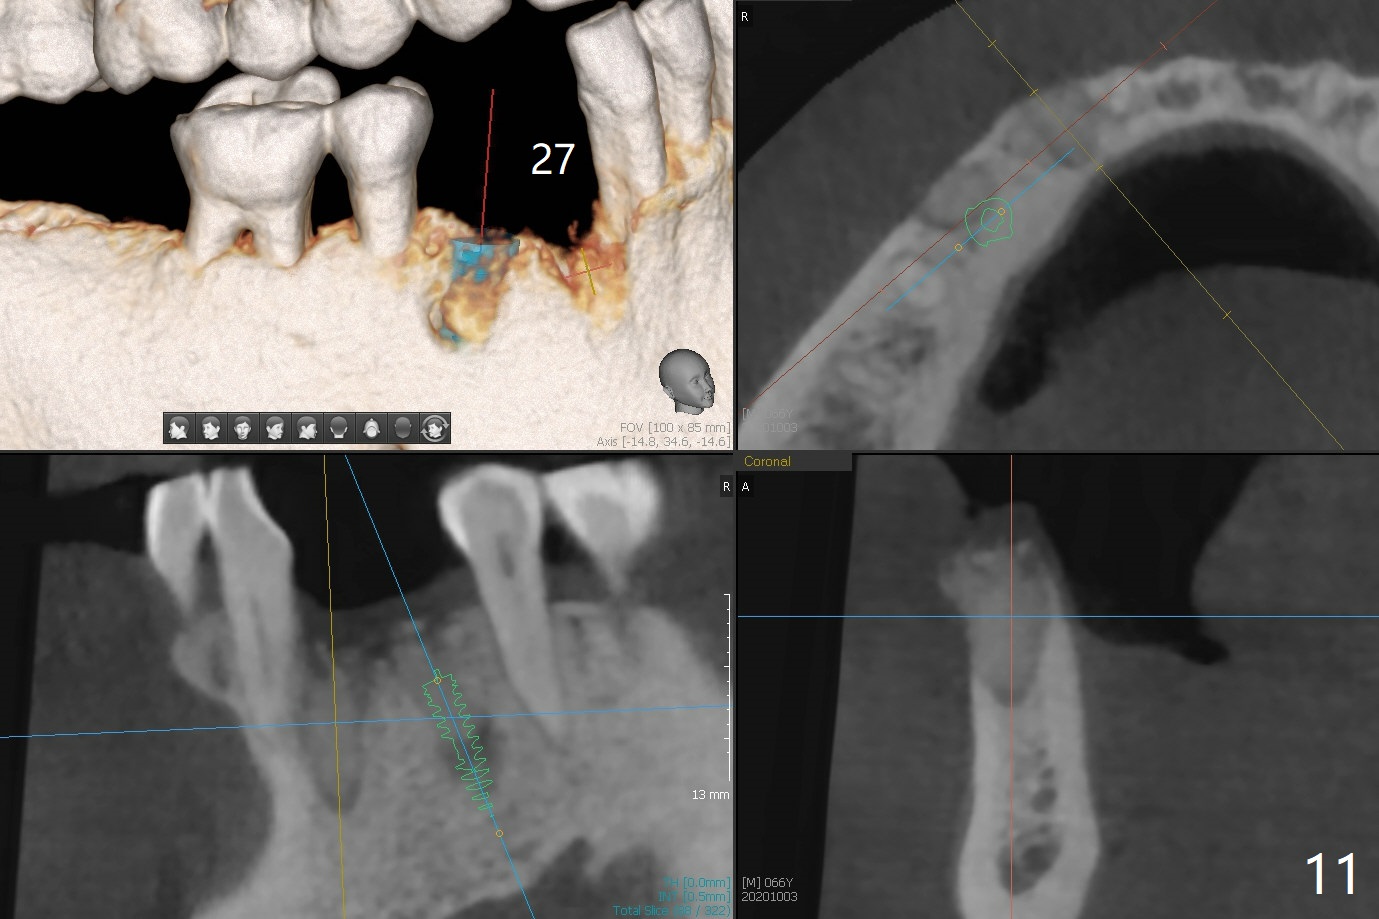

66岁男1.5年前来诊所拍摄全景片(图一),似乎27,28号牙还能保留,今天突然回来,主诉27、28区疼痛瘘道,商量决定先拔除27,28,32及右下深洗。拔除32号牙时发现它接近31区(将要植牙),必须植骨(近中部分(远中塞入胶原塞)),27,28颊侧骨板缺失(大量肉芽组织),植骨理所应当,而且必须拼命推压,但愿推到颊侧骨板,细的皮质骨没有压制感,非要加入粗的松质骨皮质骨,一张12x12毫米胎盘膜剪成两片覆盖27/28和32拔牙窝,4-0 PGA缝线固定,拍摄术后半侧全景片后(图二 (*:骨粉)),使用牙周敷料保护伤口。术后一个月27,28号牙位骨粉保持原位,而且颊侧骨板好像已经重建(图八,十一,九),似乎能植入两个植体(图十,十二)。